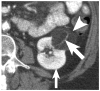

Materials and methods: We identified CT scans of 20 patients (13 women and 7 men; mean age, 63 years) with either perirenal liposarcoma (n = 11) proven at histopathology or large exophytic angiomyolipomas (n = 9) determined by 2-year stability (n = 6) or histopathology (n = 3). Two independent readers unaware of the final diagnoses recorded the presence of the following CT findings: (1) tumoral vessel extending into the renal cortex, (2) tumoral vessel extending into the renal hilum, (3) renal parenchymal defect at the site of tumor contact, (4) intratumoral hemorrhage, (5) nonfat attenuating intratumoral nodules, and (6) calcification.

Results: A tumoral vessel extending into the renal cortex was seen only in angiomyolipomas (7 and 6 of 9 patients versus 0 and 0 of 11 liposarcomas for readers 1 and 2, respectively; P < 0.005 for both). A parenchymal defect was more commonly seen in angiomyolipomas (7 and 6 of 9 angiomyolipomas versus 1 and 1 of 11 liposarcomas for readers 1 and 2, respectively; P < 0.05 for both). Calcifications were seen by both readers in 6 of 11 liposarcomas but not in any angiomyolipomas (P < 0.05). The other recorded findings were not useful in distinguishing CT features (P > 0.1 for both readers).

Conclusions: In the evaluation of a fatty perinephric mass at CT, the presence of a tumoral vessel extending into the renal cortex or a renal parenchymal defect at the site of tumor contact strongly favors the diagnosis of exophytic angiomyolipoma, whereas calcifications suggest liposarcoma.